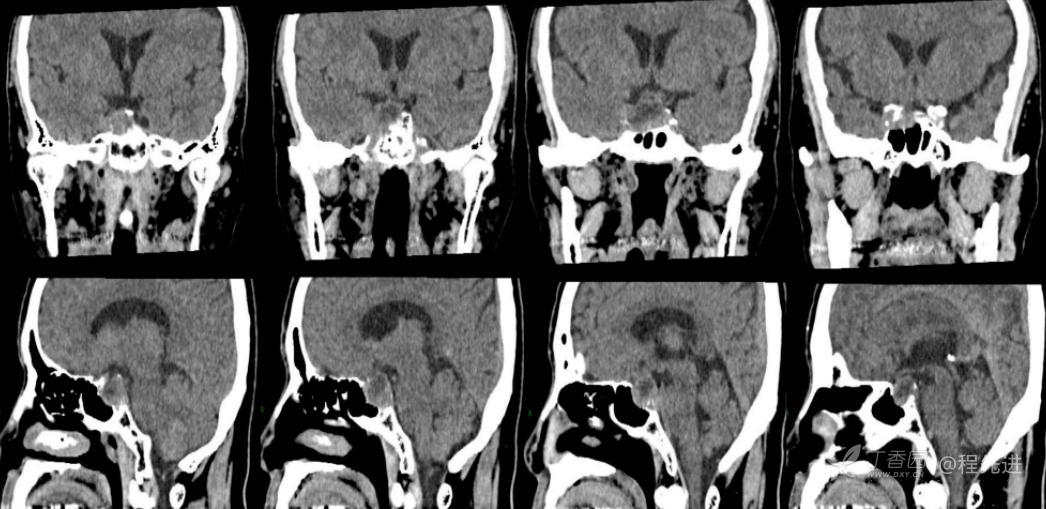

CT: